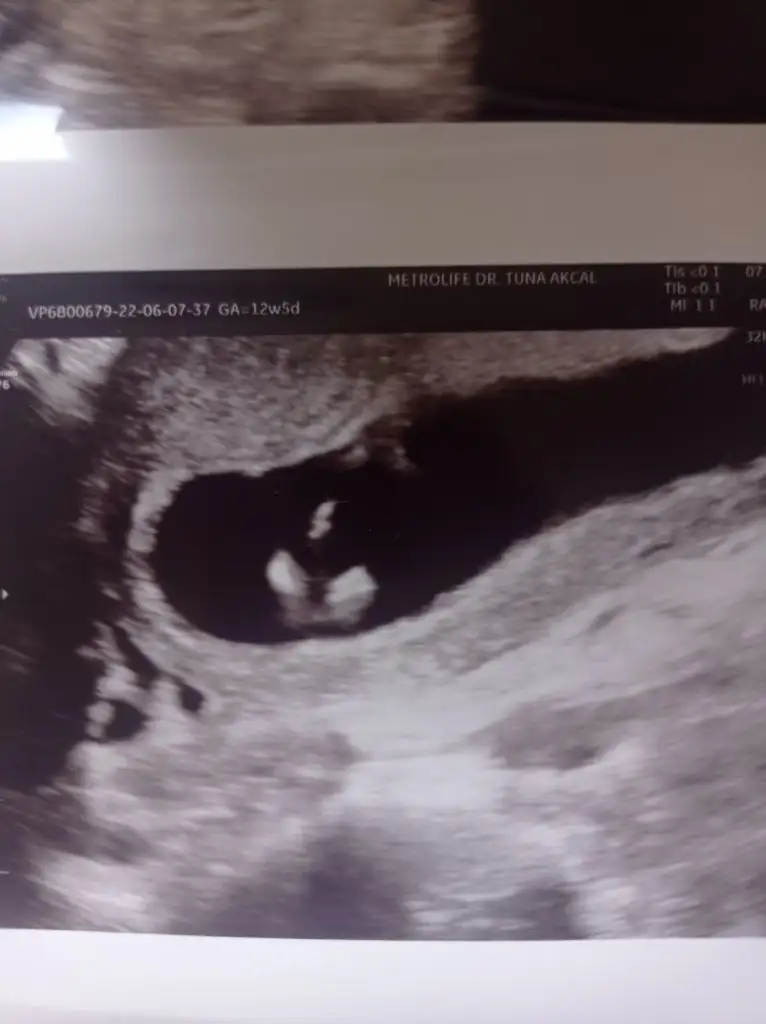

5 ve 14. haftaya kadar olan ultrason fotolarınızı paylaşın. Vajinadan mı yoksa karından mı çekildiğini ve kaç haftalık olduğunu da mutlaka belirtin.

Ve ayrıca 12 haftalıkken öğrendim ikiz olduğunu size daha önce 6 haftalıkken tahmin yaptınız erkek dediniz diye hatırlıyorumEki Görüntüle 3079866 Slm cinsiyet tahmini yaparmisiniz 12 +2

Ikiz gebelik çift yumurta ikizleri bakalım doğru çıkacakmı 12 de doktor erken dedi 2 hafta sonra randevu 16 haftalık olucam şuan 14